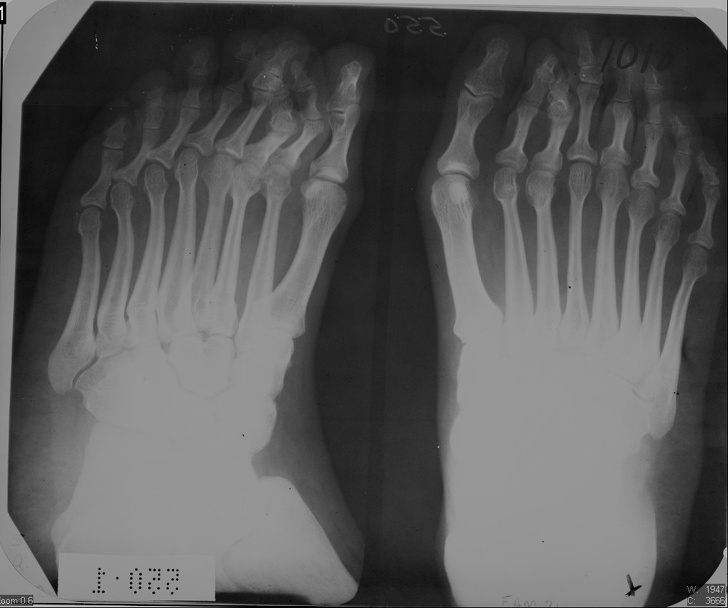

20. Рентген стоп пацієнта з полидактилией

Полідактилія — анатомічне відхилення, при якому людина народжується більш ніж з 5 пальцями на кінцівки.